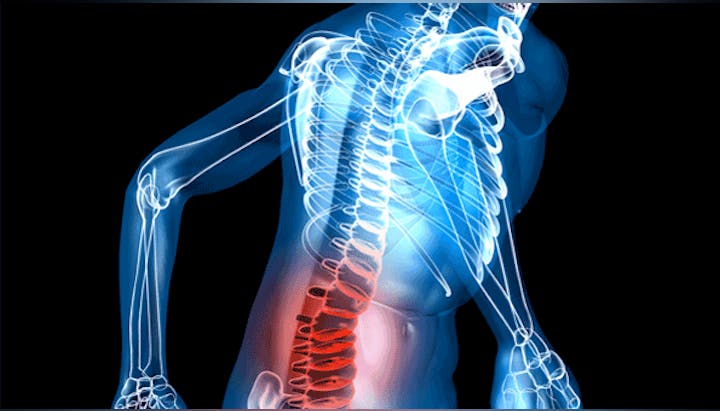

Lower Back Injuries Plague Many Athletes

Help Your Back Work For You